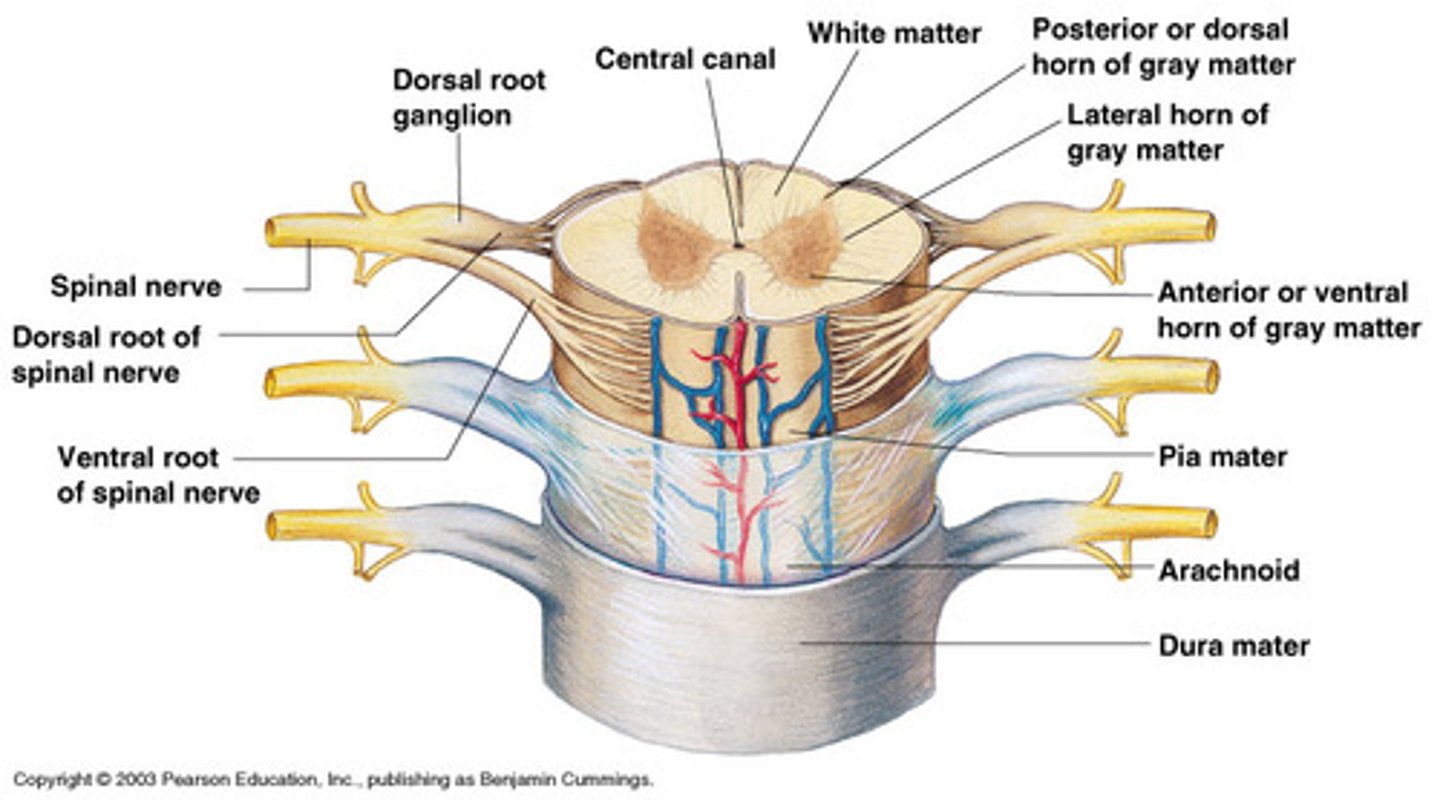

spinal cord

nerve

bundle of axons in PNS

spinal nerves

31 pairs of nerves arising from the spinal cord; letter abbreviation for region of spine they originate from; forms where the anterior and posterior roots join; mixed nerves (contain sensory and motor fibers)

posterior (dorsal) rootlets

merge to form a root

posterior (dorsal) root

contains sensory axons

posterior (dorsal) root ganglion

contains cell bodies of sensory neurons

true spinal nerve

anterior root

contains motor axons

spinal meninges

dura mater, arachnoid mater, pia mater (PAD to protect the spinal cord from deep to superficial)

dura mater (spinal cord)

thick, outermost layer of the meninges; 5 on image

arachnoid mater (spinal cord)

middle weblike layer of the meninges; 4 on image

pia mater (spinal cord)

thin, delicate inner membrane of the meninges; 3 on image

central canal of spinal cord

center of spinal cord which contains cerebrospinal fluid

posterior median sulcus

a shallow vertical groove dividing the spinal cord throughout its whole length in the midline posteriorly.

anterior median fissure

a groove along the anterior midline of the spinal cord that incompletely divides it into symmetrical halves

gray matter of the spinal cord

cell bodies, dendrites, and unmyelinated axons arranges in a butterfly shape with anterior and posterior "horns"

posterior (dorsal) horns

contain axons of sensory neurons and cell bodies (sensory nuclei) of interneurons